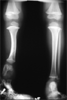

Post

Op

Congenital fibular hemimellia with proximal lengthening and distal corticotomy to correct procutvatum and valgus at tibia

Progress

Length tibia restored with correction of deformity